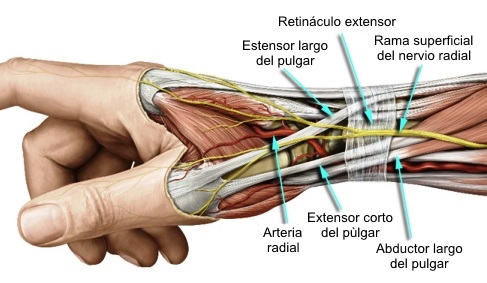

Síndrome de Wartenberg,

descrito en 1932, es el atrapamiento esencialmente de la rama

sensitiva superficial del nervio radial.

Hay muchos factores que pueden

contribuir al desarrollo del síndrome de Wartenberg.

Las causas más frecuentes de la

compresión de la rama sensitiva superficial del nervio radial son:

-

Sobreesfuerzo

-

Bandeletas de la fascia de los

extensores radiales del carpo, largo y corto.

-

Variaciones anatómicas

-

Trauma (fracturas, contusiones…)

-

Enfermedad de De Quervain

-

Masa (tumores, lipomas…)

-

Diabetes mellitus

-

Cirugías previas

-

Relojes de pulsera muy ajustados

-

Exposición repetida a frío

intenso

El sitio anatómico de compresión corresponde al

tránsito del nervio de su posición submuscular debajo del supinador

largo a su posición subcutánea en el extensor radial largo del

carpo. Especialmente con la pronación, estos 2 músculos pueden crear

un efecto como de tijera comprimiendo el nervio sensitivo radial.

Síndrome de

Wartenberg

Los pacientes con el diagnóstico de síndrome de

Wartenberg se quejan de dolor y parestesias en la superficie radial

dorsal del antebrazo con irradiación al dorso del pulgar y del

segundo y tercer dedos. Con frecuencia refieren aumento de los

síntomas con el movimiento de la muñeca o aparecen cuando se

aprietan los dedos pulgar e índice. Estos pacientes presentan la

prueba de Tinel positiva cuando se percute sobre el ligamento

carpiano palmar. El paciente refiere la sensación como un pinchazo o

una descarga eléctrica sobre la estiloides radial. Al tratarse de un

nervio sensitivo, hay trastornos sensitivos, pero no existe atrofia.

La hiperpronación del antebrazo puede causar un signo de Tinel

positivo. Un alto porcentaje de estos pacientes en la exploración,

revelan hallazgos similares a los de la tenosinovitis de Quervain.